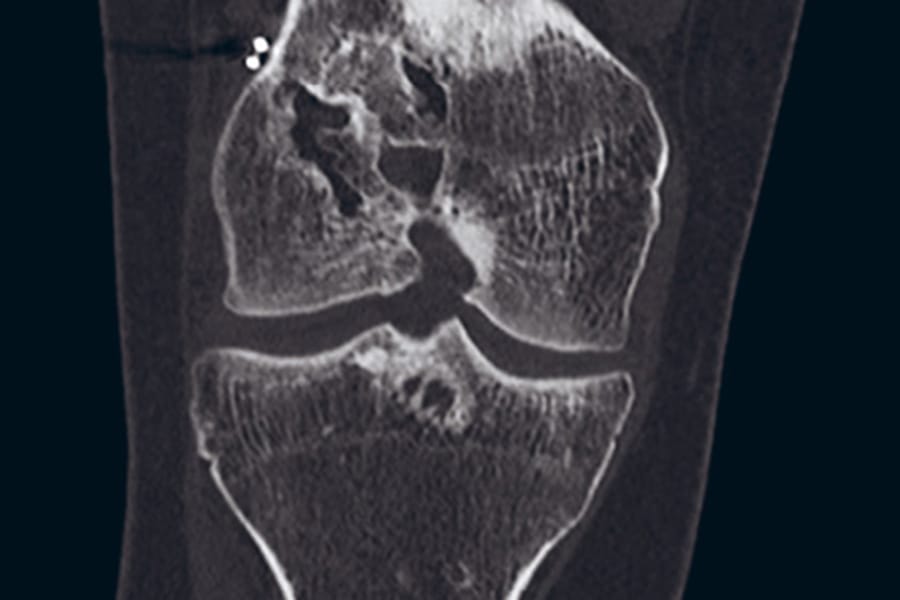

The clinical articles address diverse subspecialties. Trapeziometacarpal joint imaging in the surgical management of basal thumb arthritis informs operative planning in hand surgery, while orthopaedic surgical site infection prevalence in Egypt contributes epidemiological data on infection control. Ligamentous reconstruction is examined through revision ACL reconstruction, and implant selection is explored in the context of short stems for obese patients. The issue concludes with an anatomical and fluoroscopic review of percutaneous screw fixation of the pelvic ring and acetabulum.